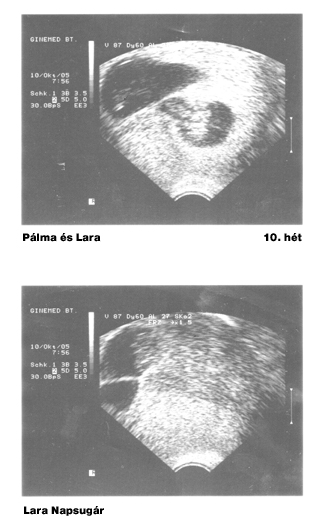

És íme a legelső UH-fotók a babákról:

Vadvirág